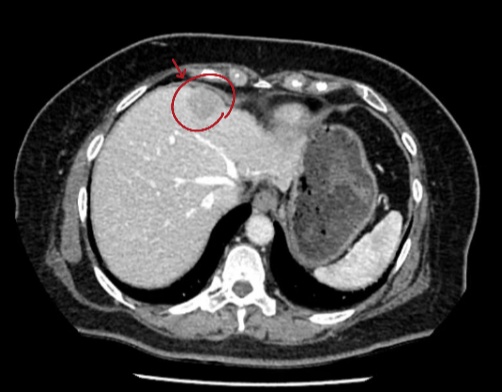

患者术前CT

利用术前CT,进行三维重建。